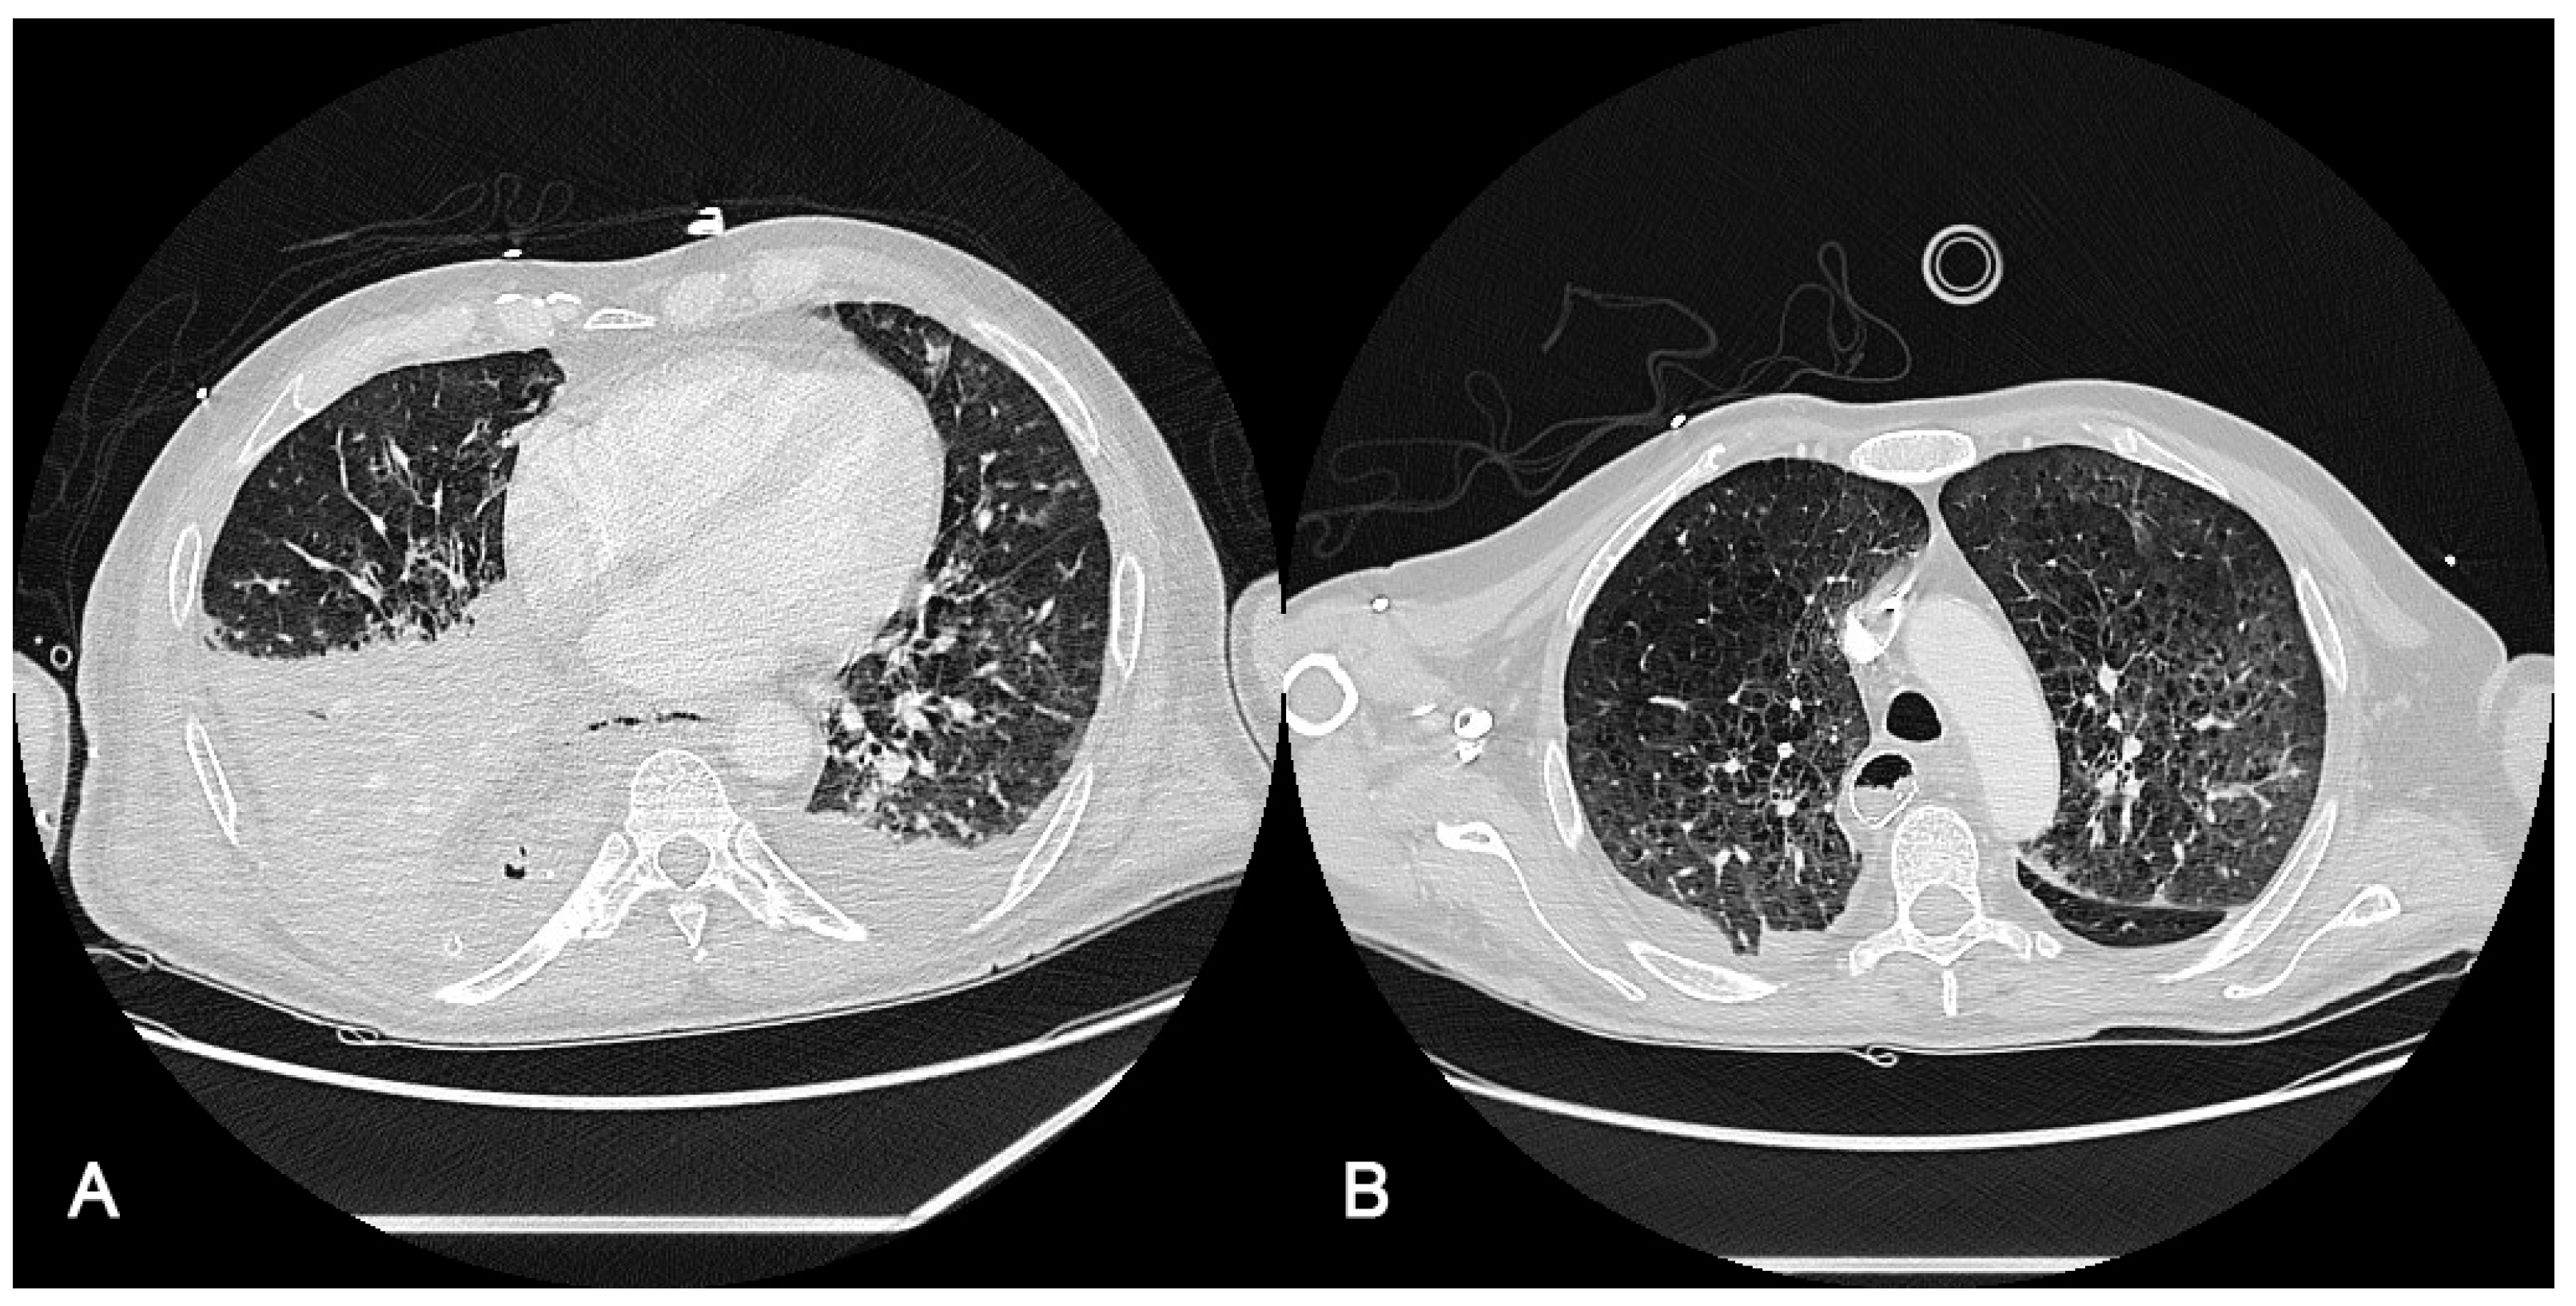

Radiological findings of case 3 (coronavirus disease with spontaneous pneumothorax and persistent air leak after chest drainage) are shown in Figure 3 and Figure 4.

Thorax X-ray findings of case 3. (A) Massive left pneumothorax. (B) Apical left pneumothorax (red arrow) with partial reexpansion after pleural drainage (blue arrow). (C) Incomplete lung reexpansion and air leak after second pleural drainage (blue arrow).

Figure 4.

Radiological findings of case 3. Case #3: (A) At ICU Admission: Pulmonary thromboembolism with signs of pulmonary hypertension. Bilateral alveolar interstitial infiltrate due to pneumonitis secondary to SARS-Cov-2 infection. (B) Anterior pneumothorax (red arrow) with partial atelectasis and bilateral alveolar infiltrate with lower density and extension. (C) At discharge, 3 months after admission, a clinically significant improvement in the alveolar-interstitial infiltrates and resolution of the pneumothorax are evident.